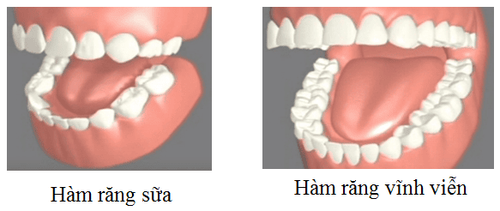

Răng sữa và răng vĩnh viễn là 2 loại răng hoàn toàn khác nhau nhưng lại có mối qua hệ vô cùng mật thiết. 2 răng này rất khó để phân biệt bởi răng sữa đa số sẽ được thay thành răng vĩnh viễn nhưng có một số nhóm răng khi mọc lên mà không hề thay răng. Vậy răng sữa là gì và răng vĩnh viễn là răng gì và làm sao phân biệt được răng sữa và răng vĩnh viễn? Bài viết sẽ giúp bạn đọc hiểu rõ hơn về 2 loại răng này.

Một đứa trẻ sẽ bắt đầu mọc răng vào khoảng từ 4-6 tháng tuổi và hoàn thành lúc 2 tuổi rưỡi. Số lượng răng tất cả có 20 chiếc răng sữa. Trong đó:

Đến khoảng 12 tuổi răng sữa của trẻ sẽ được thay hết, trẻ có 28 – 32 chiếc răng vĩnh viễn